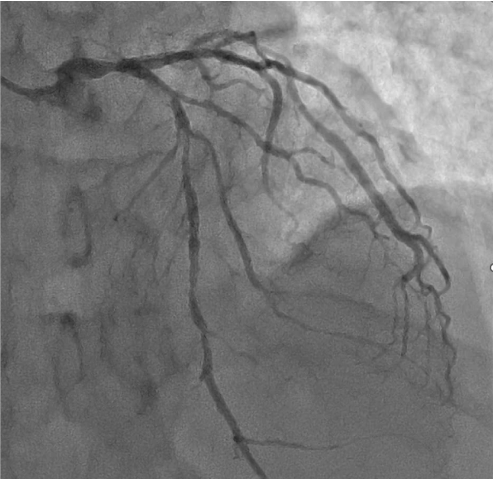

LCA CAG

-